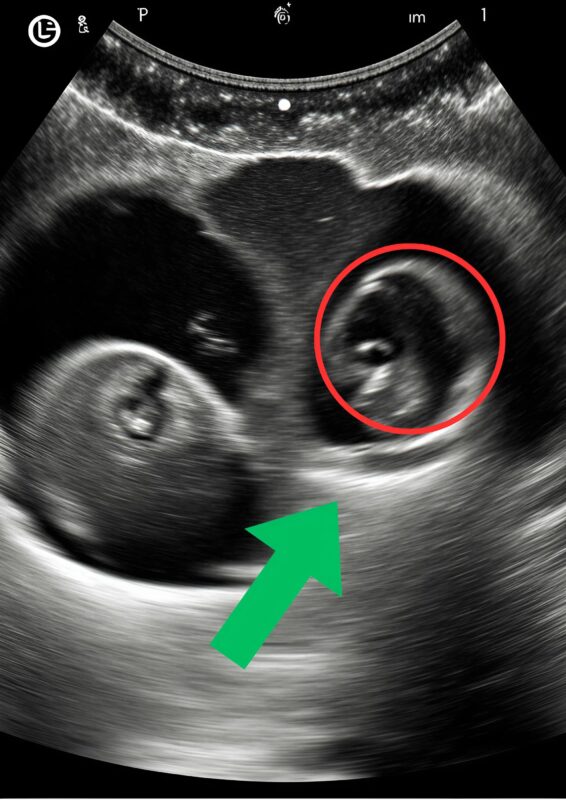

Then came the moment when he applied the gel and placed the ultrasound wand on my belly . I watched the screen with rapt attention, expecting the familiar flicker of tiny movements, the rhythmic heartbeat of the little life growing inside me

. But as the seconds stretched, the doctor’s expression began to shift — a small twitch at the corner of his mouth, his eyes widening just slightly

.

“Uh… hmm…” he muttered, scanning the screen with a careful precision that made me lean forward, my heart skipping beats . “You’re… well… you’re having twins.”